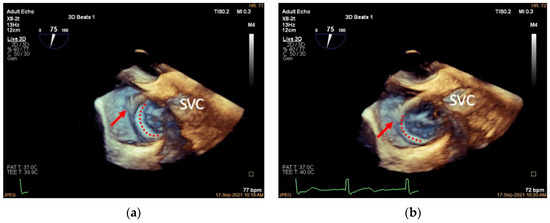

3.2. Introducing the Delivery System (Mid-Esophageal Bicaval View)